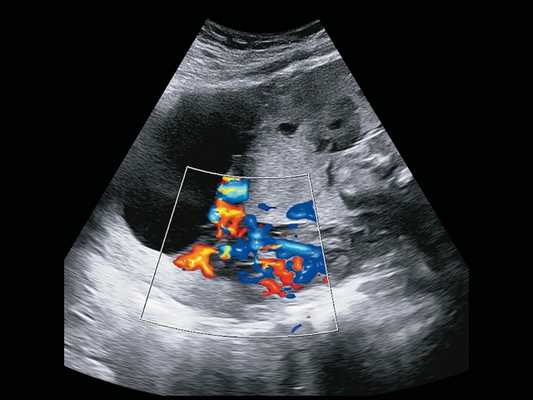

ЦДК-цветное доплеровское картирование

- Допплерометрия кровотока сосудов в системе мать-плацента-плод.

- ЦДК сосудов плаценты при монохориальном типе плацентации (при наличии условий для коагуляции анастомозов при ФФТС с 20-22 недель).

- Допплерометрия маточно - плодово - плацентарного кровотока

Монохориальные двойни имеют одну общую плаценту. Практически в 100% случаев в общей плаценте имеются многочисленные сосудистые анастомозы, связывающие напрямую системы кровообращения обоих плодов. Плацентарные анастомозы бывают артерио -артериальные (АА), вено-венозные (ВВ) и артериовенозные (АВ) [2]. Все эти анастомозы могут располагаться и на поверхности плаценты, и в глубине. И если АА- и ВВ-анастомозы в большинстве случаев скомпенсированы, то АВ-анастомозы, где кровь из артерий одного плода дренируется напрямую в вены другого плода, являются причиной многочисленных осложнений.

По статистике, течение беременности при монохориальных двойнях осложняется в 10-15% случаев фето-фетальными трансфузионными синдромами (ФФТС) разной степени тяжести 5, причем клинические проявления ФФТС зависят от наличия именно АВ-анастомозов, их количества и размеров. Классический ФФТС диагностируется обычно на сроках от 16 до 26 нед и характеризуется наличием маловодия, максимальный вертикальный карман (МВК) менее 2 см у плода-донора, и многоводием, МВК более 8 см у плода-реципиента. Практически одновременно с этим первым признаком ФФТС при ультразвуковом исследовании (УЗИ) выявляется второй признак: у плода-донора мочевой пузырь или не визуализируется, или бывает значимо маленьким, а у реципиента - переполнен, или значимо большой. Эта самая частая форма ФФТС в настоящее время называется синдромом олигурии-полиурии (TOPS), связана с наличием крупных АВ-анастомозов на поверхности плаценты, приводящих к гиперволемии плода-реципиента и гиповолемии плода-донора. При своевременной ультразвуковой диагностике эта форма поддается антенатальной коррекции фетоскопической лазерной коагуляцией АВ-анастомозов.

При наличии глубоких АВ-анастомозов малого диаметра (до 1 мм) и в отсутствие компенсирующих АА-анастомозов в 3-5% случаев у монохориальной двойни может развиваться еще одна форма ФФТС - синдром анемии-полицитемии (TAPS), когда по мельчайшим анастомозам происходит хроническое медленное кровотечение от донора к реципиенту [6]. При УЗИ количество околоплодных вод может быть приблизительно одинаково нормальным, и заподозрить TAPS можно, если обратить внимание на разницу в толщине и эхогенности территорий плацент донора и реципиента. При измерении пиковой систолической скорости (ПСС) в средней мозговой артерии (СМА) каждого плода подтверждается, что у плода с признаками анемии с ПСС выше 1,5 МоМ территория плаценты утолщена, эхогенность ее повышена, а у реципиента с признаками полицитемии с ПСС ниже 1,0 МоМ территория плаценты обычной толщины и низкой эхогенности. В случае ФФТС в виде TAPS в отличие от TOPS существующие методы пренатального лечения не так эффективны, так как мелкие глубокие АВ-анастомозы практически не видны при фетоскопии. Некоторые специалисты проводят полную лазерную дихорионизацию плаценты по сосудистому руслу с предварительной амниоинфузией. Методом выбора является внутриутробная гемотрансфузия плоду-донору, однако она эффективна только в отсутствие значимо крупных анастомозов, усугубляющих полицитемию плода-реципиента. Таким образом, эффективность однократной гемотрансфузии плоду-донору имеет и лечебное, и диагностическое значение. В противном случае некоторые специалисты проводят обменные гемотрансфузии с возмещением реципиенту объема изъятой крови физиологическим раствором [7]. Так как в большинстве случаев TAPS возникает после 26 нед, все мероприятия направлены на продление беременности с целью достижения периода жизнеспособности плодов.

Рис. 1. Беременность 28 +6 нед. Ретроплацентарные лакуны, отсутствие нормальной гипоэхогенной ретроплацентарной зоны, истончение миометрия, гиперваскуляризация пузырно-маточной зоны. Режим ЦДК.

Рис. 3. Беременность 28 +6 нед. Васкулярная инвазия в шейку матки. Режим ЦДК.

Рис. 4. Беременность 32 +4 нед. Ретроплацентарные лакуны, отсутствие нормальной гипоэхогенной ретроплацентарной зоны, истончение миометрия, выпячивание плаценты.

Рис. 5. Беременность 32 +4 нед. Ретроплацентарные лакуны, отсутствие нормальной гипоэхогенной ретроплацентарной зоны, истончение миометрия, гиперваскуляризация пузырно-маточной зоны. Режим ЦДК.

Рис. 7. Беременность 32 +4 нед. Режим LumiFlow™: сосудистые мостики (rail sign) из миометрия сквозь серозный покров в стенку мочевого пузыря (стрелки).

В режиме серошкального сканирования все ранее идентифицированные особенности плацентации (PAS 3a): ретроплацентарные лакуны, васкулярная инвазия в шейку матки, исчезновение нормальной гипоэхогенной ретроплацентарной зоны, истончение миометрия, выпячивание плаценты, гиперваскуляризация пузырно-маточной зоны были подтверждены.

Дополнительное использование технологии стереоскопической визуализации кровотока (LumiFlow™) позволило визуализировать вовлеченность стенки мочевого пузыря беременной в конгломерат тканей аномальной плацентации (сосудистые мостики (rail sign) из миометрия сквозь серозный покров в стенку мочевого пузыря), то есть идентифицировать placenta percreta (PAS 3b). Проведенная в последующем МРТ констатировала полное предлежание плаценты с прорастанием в рубец, через все слои миометрия, шейку матки и цервикальный канал (рис. 8) и верхнюю стенку мочевого пузыря.